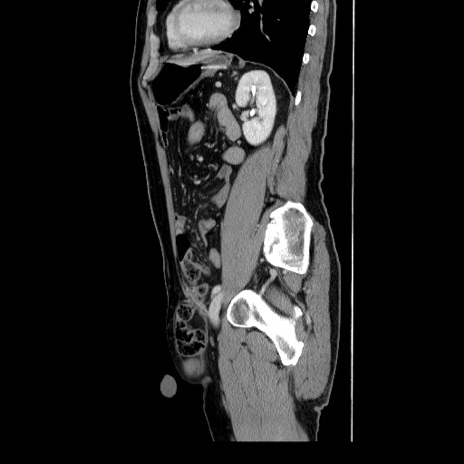

症例34(矢状断像)

【症例】60歳代 男性

【主訴】右鼠径部膨隆

【現病歴】1年程前より右鼠径部膨隆あり。自己にて還納可能だったため放置していた。3時間前より右鼠径部の脱出を認め、還納困難となり受診。

【身体所見】右鼠径部に小児頭大の膨隆あり。弾性硬であり、用手還納は困難。左鼠径部にも膨隆を認める。脱出はなし。